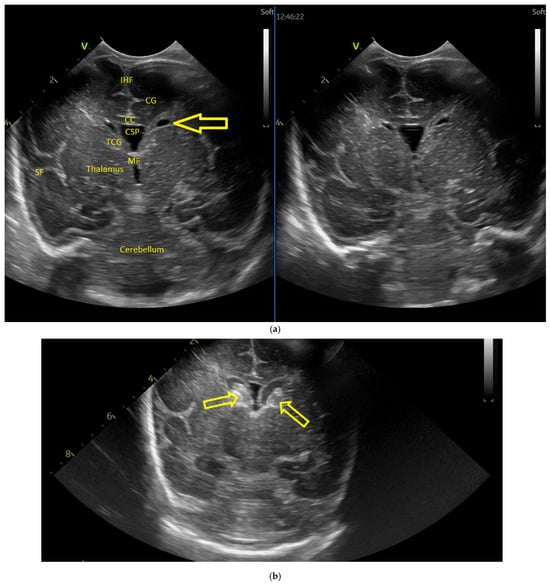

Five weeks after birth, the patient presented for the first cranial ultrasound examination, which revealed enlarged ventricles and the presence of a hyperechoic image in the right frontal lobe, suggestive of calcifications. The parenchymal tissue was reduced (Figure 4a–d). The anterior fontanelle was wide, with large sutures. The neurological assessment showed that the infant could keep eye contact and would also hold its head during the traction-to-sit maneuver but was not able to lift its head while in the prone position. The passive tone assessment showed the “scarf sign”, with the elbow at the midline and a popliteal angle range for both legs of 90–100°. Deep tendon reflexes were present. The general movement (GM) assessment revealed a poor repertoire pattern with minimal mobility in the lower limbs. Treatment for Toxoplasma was initiated.

(a) Cranial ultrasound. Coronal view. Lateral ventricles and third ventricle enlargement. L1, L2—Levine index measurement. L3, L4—posterior horn of the lateral ventricles’ width measurement. L5—third ventricle width measurement (personal image collection). (b) Cranial ultrasound. Sagittal view. Enlarged third and fourth ventricles. L1, L2—third ventricle measurements. L3, L4—fourth ventricle measurements (personal image collection). (c) Cranial ultrasound. Sagittal view. Enlarged lateral ventricles. Up—left ventricle. Down—right ventricle (personal image collection). (d) Cranial ultrasound. Coronal view. Punctuate hyperechoic images were observed in the right lobe (personal image collection). (e). Up left—MRI T1 sequence. Up right—MRI T2 sequence—susceptibility weight imaging (SWI). Down—CT scan. Transversal view. Yellow arrows—multiple calcifications can be seen in the CT scan (personal image collection). (f) Cranial ultrasound. Coronal view. Lateral ventricles. L1, L2—Levine index measurement. L3, L4—anterior horn width measurement. Blue arrow—intraventricular shunt (personal image collection). (g) Cranial ultrasound. Sagittal view. Thalamo-occipital distance measurements. Up—right ventricle. Down—left ventricle (personal image collection).

At six weeks after birth, an MRI scan was performed, while a CT scan was performed at 14 weeks of life, both providing valuable information regarding the sequelae of Toxoplasmosis (Figure 4e). Even though a few signs were observed on the MRI, the CT scan better outlined the presence of the parenchymal calcifications. A neurosurgical intervention was intended, a ventricle puncture was performed, and a shunt was placed in the right ventricle. The cranial ultrasound at two months of life did not show notable improvements, however (Figure 4f,g). The neurological examinations showed axial hypotonia and limb hypertonia.

Case 5 involved a 35-week gestational age newborn who presented with birth asphyxia and required resuscitation after delivery, which involved a balloon and mask and then a balloon and laryngeal mask, and afterwards mechanical ventilation in the NICU (Neonatal Intensive Care Unit) with SIMV/IPPV (synchronized intermittent mandatory ventilation/invasive positive pressure ventilation), who was antenatally diagnosed through MRI with subacute polyhydramnios and ventriculomegaly due to a suspected medulla oblongata tumor (Figure 5a).

(a,b) MRI—T2 sequence. Sagittal view. Antenatal. Yellow arrows indicate the place of the suspected tumor (personal image collection). (c) Cranial ultrasound. Sagittal view. Up—enlarged left ventricle. D1—thamalo-occipital distance. Down—enlarged right ventricle. D1—thalamo-occipital distance (personal image collection). (d) Cranial ultrasound. Sagittal view. Enlarged third ventricle. Fourth ventricle is normal. D1, D2—measurements of the third ventricle (personal image collection). (e) Cranial ultrasound. Transtemporal view. Enlarged third ventricle. Sylvian aqueduct is not visible. D1—measurement of third ventricle. LV AH—lateral ventricle anterior horn. LV OH—lateral ventricle occipital horn. V 3—third ventricle (personal image collection).

After stabilization, the cranial ultrasound exam revealed enlargement of the lateral ventricles and third ventricle, with a normal fourth ventricle. There was no visualization of the Sylvian aqueduct, which raised the suspicion of aqueduct atresia or stenosis (Figure 5c–e). There was no improvement seen in the cranial ultrasound examinations that followed.